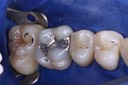

Photos of Clinical Operations

Mentors: Drs. Randy Allan, Greg Card, Peter Kearney

Clubs #44 and #50 joint meeting